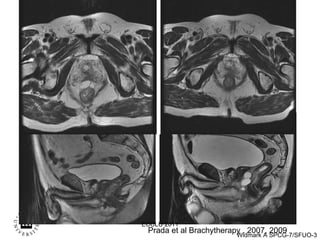

Prada et al Brachytherapy , 2007, 2009 ECCLU 2011

Prada et alBrachytherapy , 2007, 2009 ECCLU 2011